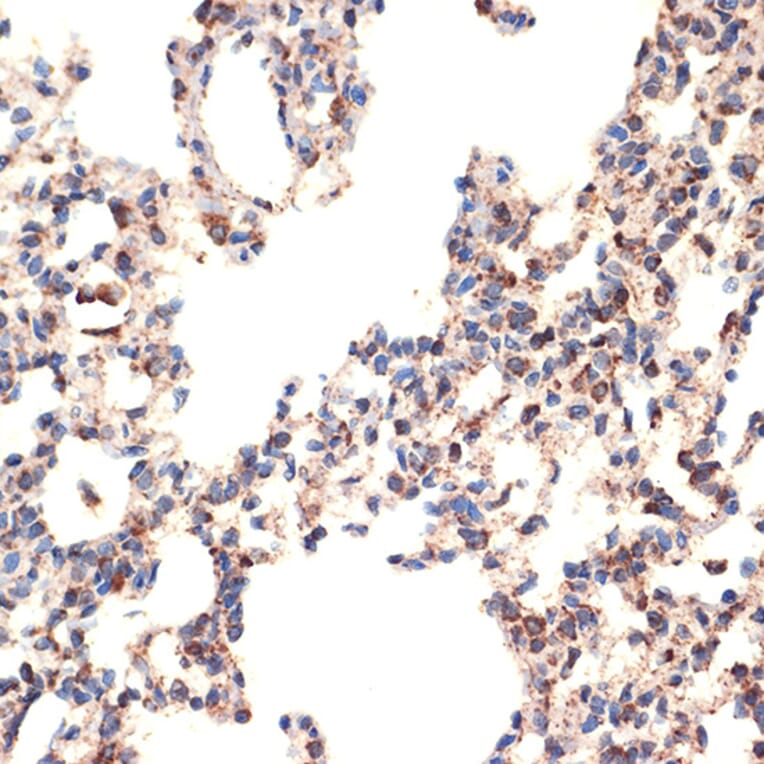

Immunohistochemistry analysis of paraffin-embedded rat lung using Anti-Bcl G/BCL2L14 Antibody [ARC2474] (A307106) at a dilution of 1:100 (40x lens). Perform microwave antigen retrieval with 10 mM Tris/EDTA buffer pH 9.0 before commencing with IHC staining protocol.